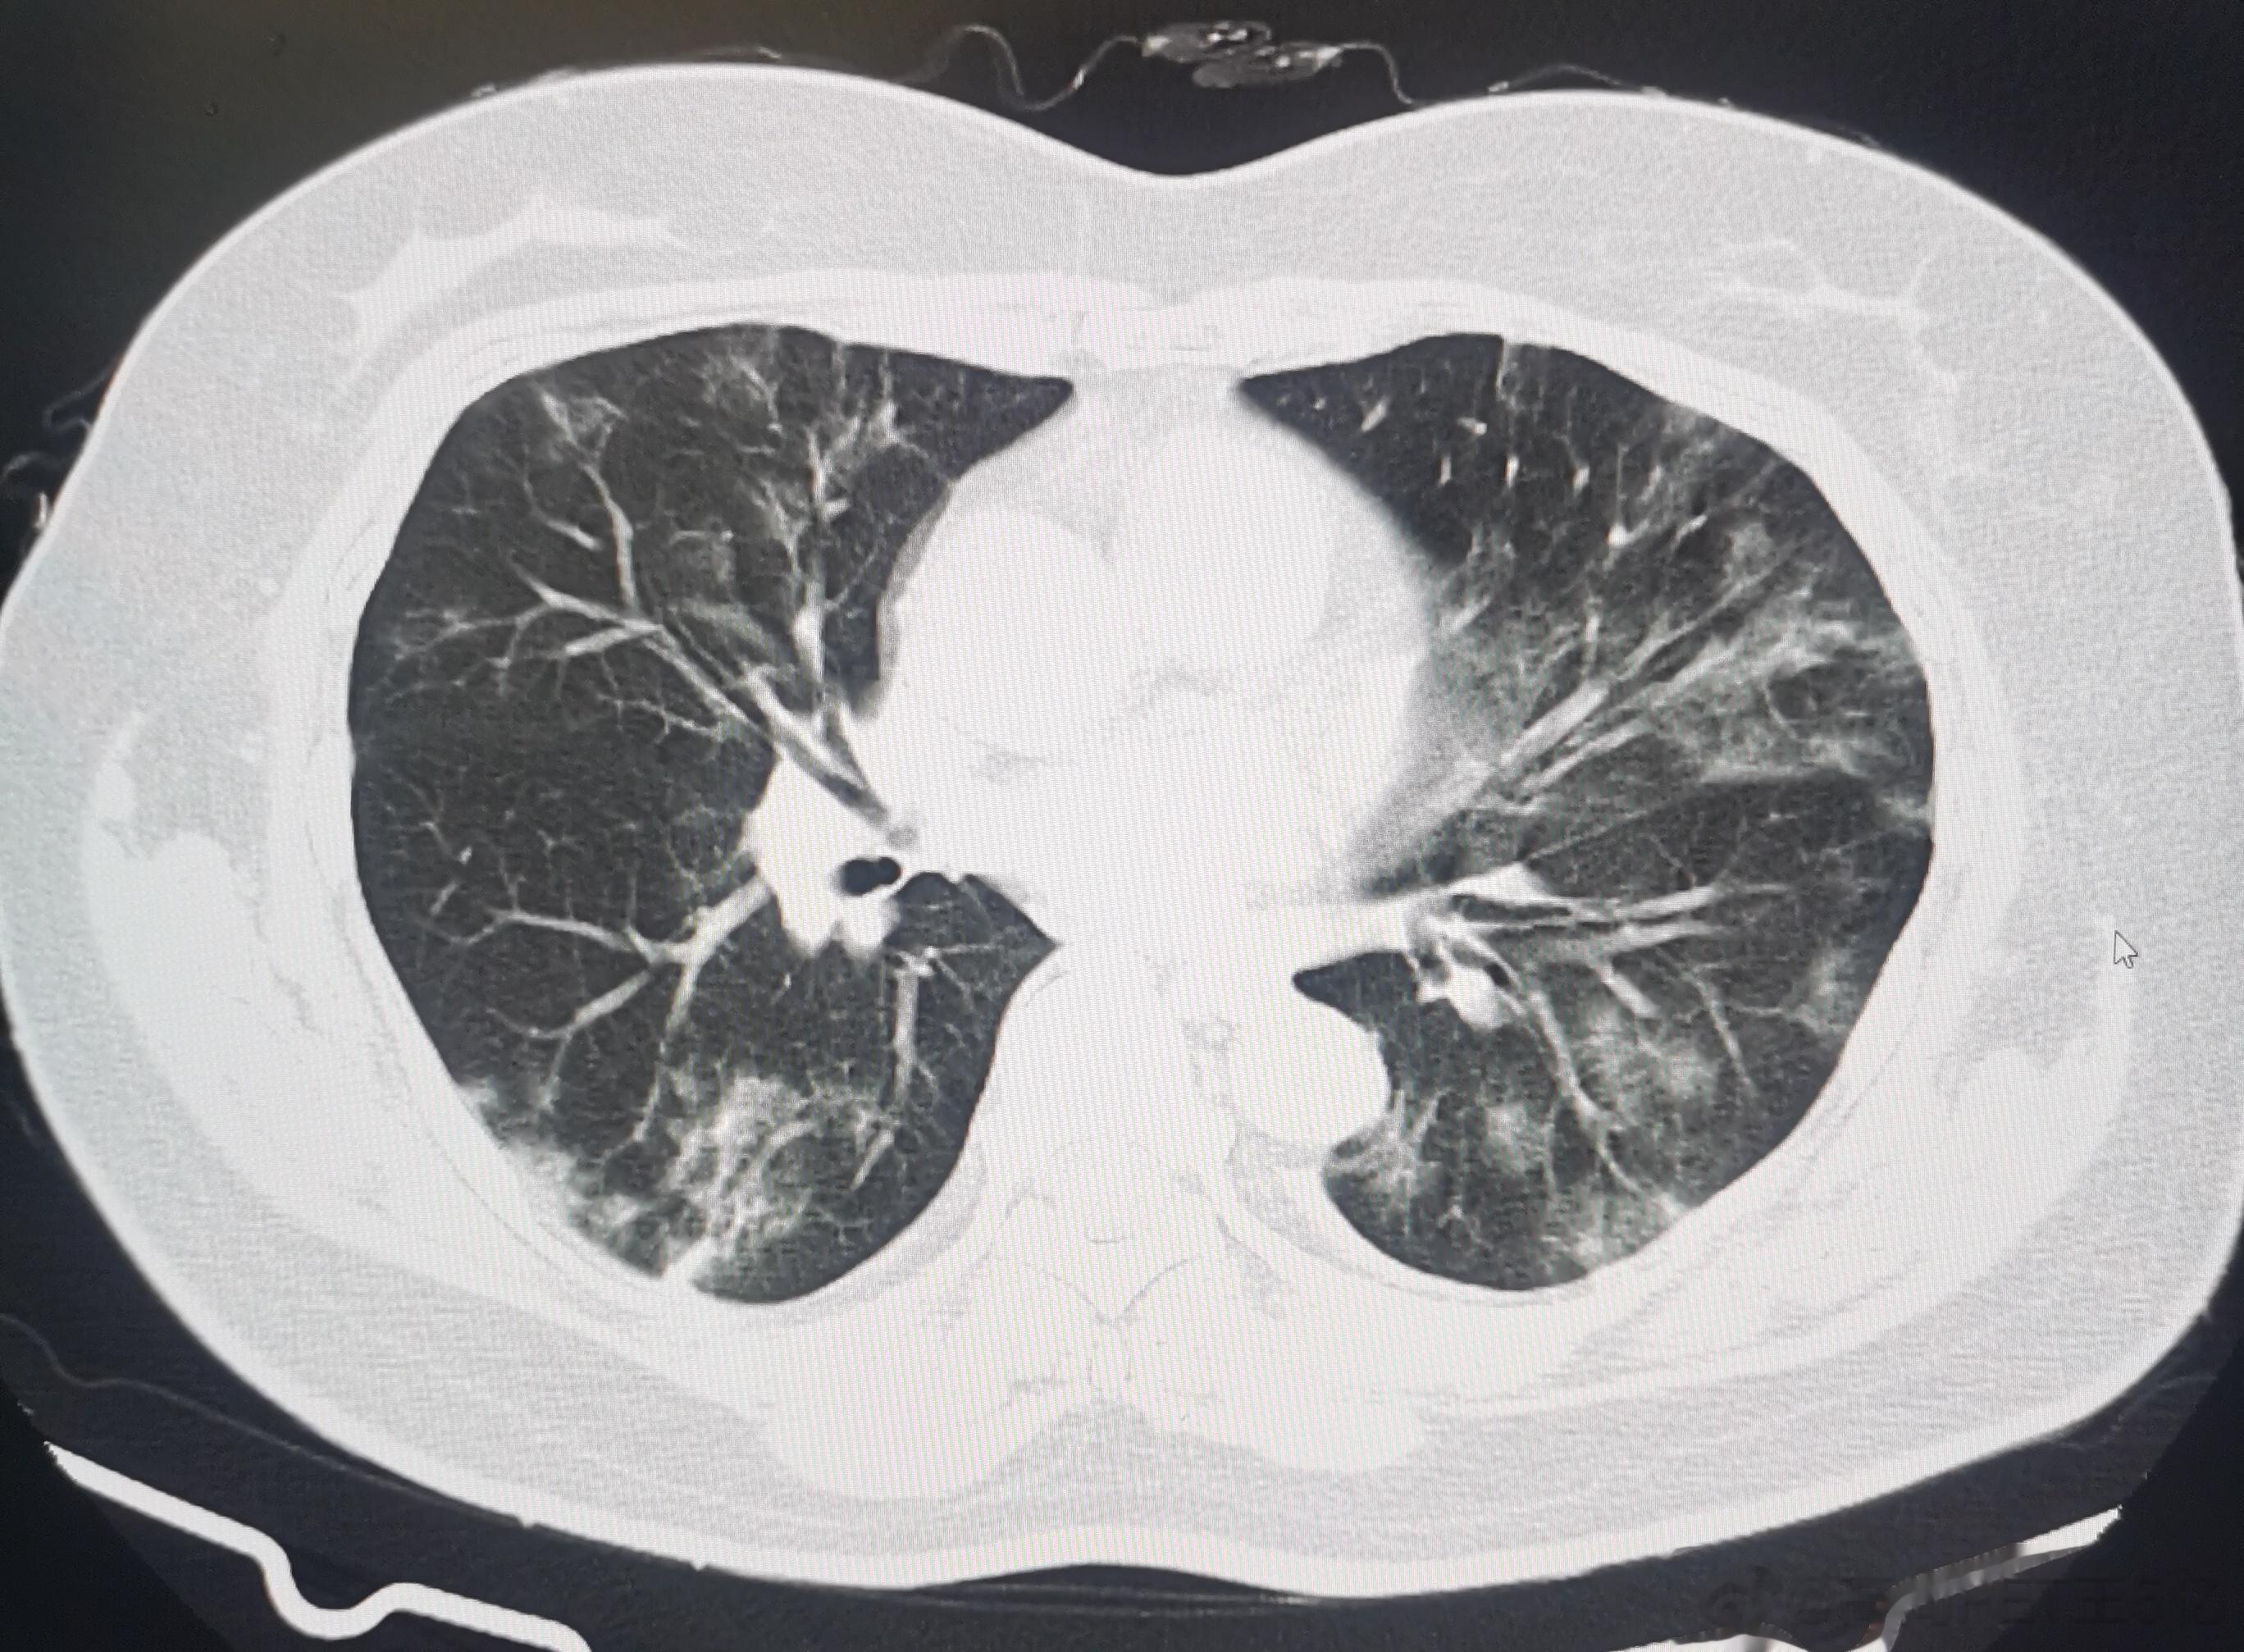

今日我们高尚影像中心新冠肺炎筛查病人是108例,其中28例有轻度新冠肺炎影像表现,检出率接近26%,最最小14岁(下面第一排CT图像),最大年龄是87岁(下面第二排CT图像),大部分人的年龄超过60例。由此可以看出,新冠病毒肺炎可能会累及各个年龄段,但主要还是60岁以上老年人群。如果新冠感染超过2周咳嗽症状还不减轻者,最好做一个胸部CT判断有无新冠病毒肺炎,这对于决策治疗方案及预测治疗效果都很关键。#老年人感染新冠后小心肺炎##感染新冠都要做CT吗#

今日我们高尚影像中心新冠肺炎筛查病人是108例,其中28例有轻度新冠肺炎影像表现,检出率接近26%,最最小14岁(下面第一排CT图像),最大年龄是87岁(下面第二排CT图像),大部分人的年龄超过60例。由此可以看出,新冠病毒肺炎可能会累及各个年龄段,但主要还是60岁以上老年人群。如果新冠感染超过2周咳嗽症状还不减轻者,最好做一个胸部CT判断有无新冠病毒肺炎,这对于决策治疗方案及预测治疗效果都很关键。#老年人感染新冠后小心肺炎##感染新冠都要做CT吗#